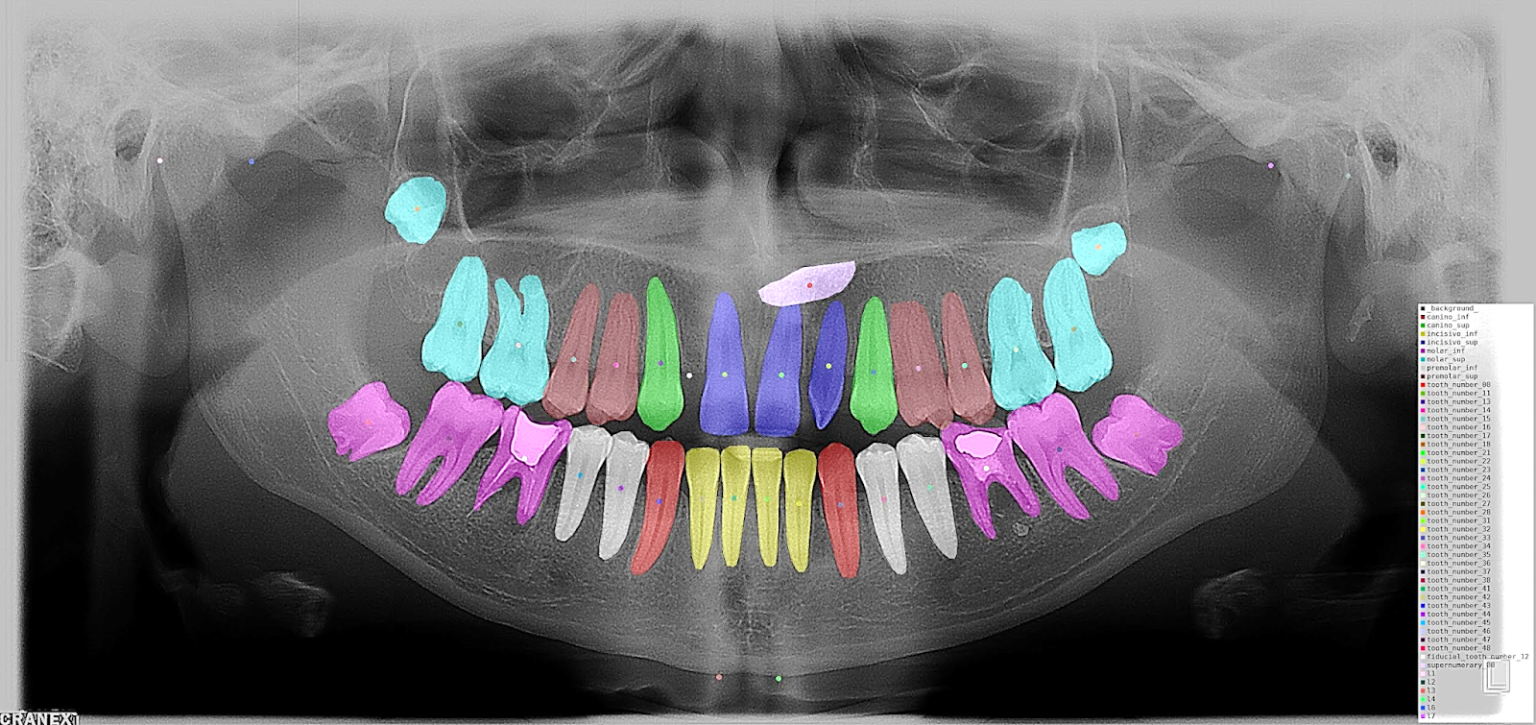

Desarrollo de algoritmos de IA para el diagnóstico temprano de patologías dentales mediante análisis de imágenes radiográficas.